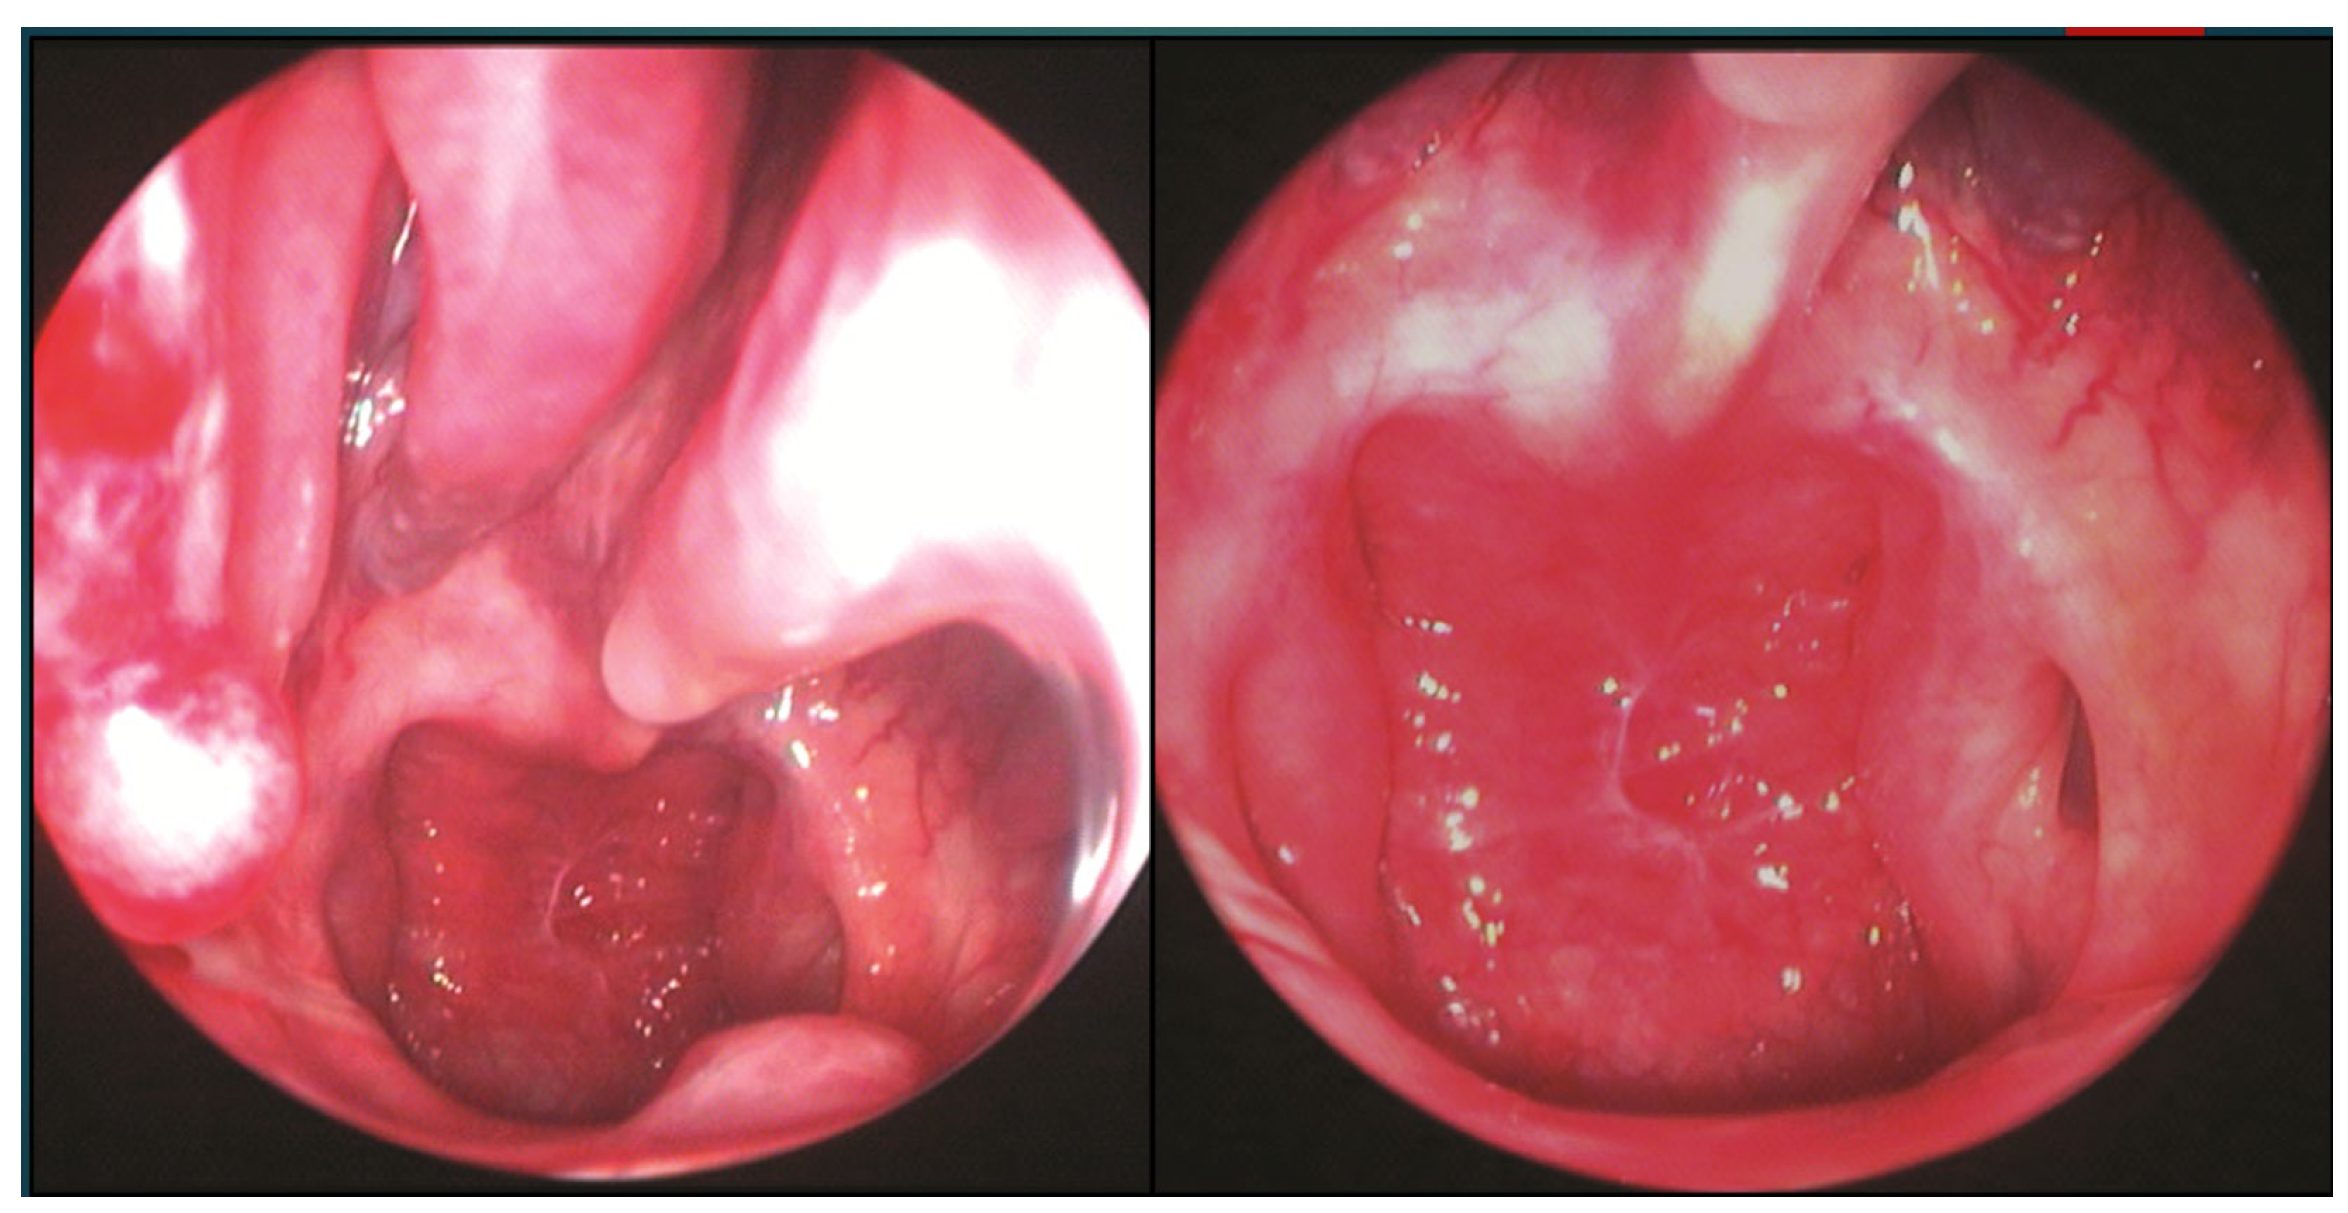

The patient underwent endoscopic ENT follow-up 4 days after the operation and 30 days later (Figure 6).

Figure 6. ENT 4 days after surgery and 30 days later.